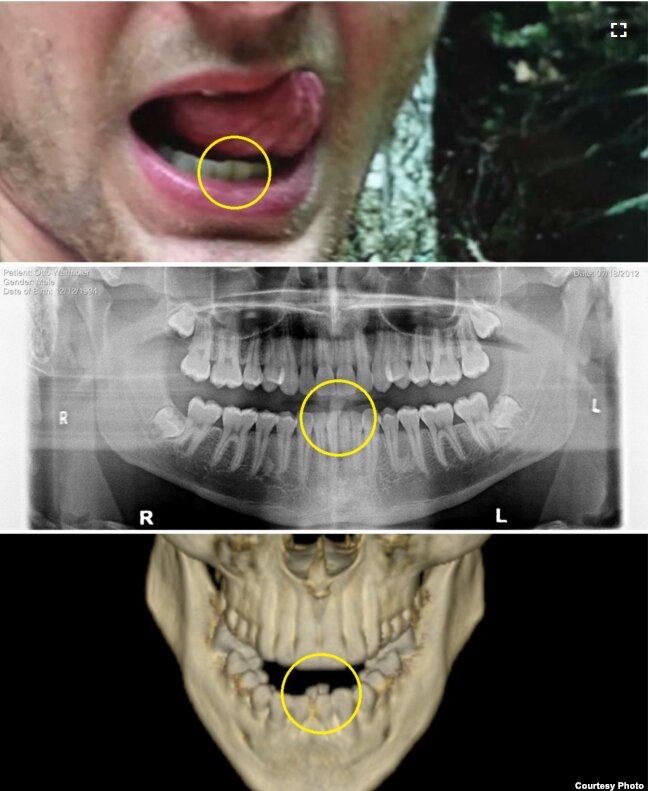

北朝鮮が拷問か 死亡の米大学生の歯列変形。米メディアが写真公開 高英起-。

北朝鮮解放後死亡した米学生、両親は「組織的な拷問」だったと - BBCニュース。

社説 北朝鮮解放の米学生が受けた仕打ち - WSJ。

北朝鮮、米に2億円超を請求か 解放後に死亡の米学生の医療費で -。

オットー・ウォームビアに北朝鮮は何をしたのか? 語られない人質の真実GQ JAPAN。